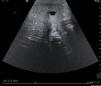

Presentamos el caso de un lactante varón de 2 meses, primer hijo de padres jóvenes sanos, fruto de un embarazo controlado, sin incidencias y serologías maternas negativas, que se remitió a nuestra institución para un estudio por ictericia y acolia presentes desde el nacimiento. La analítica al ingreso mostraba bilirrubina total de 7,96mg/dl, bilirrubina directa de 4,3mg/dl, hipertransaminasemia (alanino-aminotransferasa [ALT] de 247U/l y aspartato-aminotransferasa [AST] de 153U/l, gammaglutamiltransferasa [GGT] de 720U/l) y elevación de colesterol. Las serologías para virus hepatotropos fueron negativas. La ecografía abdominal evidenciaba un hígado homogéneo sin lesiones observables, discretamente aumentado de tamaño, sin otros hallazgos patológicos. La gammagrafía realizada (p-isopropil acetaniliodoiminodiacético [PIPIDA]) mostraba captación hepática disminuida, con marcada eliminación renal del radioisótopo y sin actividad a nivel intestinal en ninguna de las detecciones, incluidas las tardías. La sospecha de atresia de vías biliares se confirmó en la cirugía y se realizó portoenterostomía de Kasai a los 79 días de vida. Se inició, según el protocolo de nuestra sección, tratamiento con prednisona intravenosa 4 días en pauta decreciente (40, 30, 20 y 10mg, respectivamente) y con antibiótico intravenoso de amplio espectro durante 10 días (piperacilina-tazobactam y gentamicina). Asimismo, una vez recuperada la tolerancia por vía oral se añadió ácido ursodesoxicólico en dosis habituales y vitaminas liposolubles. A los 3 días de la cirugía, el paciente recuperó el flujo biliar (deposiciones teñidas) y a los 10 días de la intervención, dada su buena evolución, se procedió al alta hospitalaria con los tratamientos antes comentados; se añadió profilaxis antibiótica oral con amoxicilina-clavulánico (15mg/kg/día en dosis única) para mantener durante el primer año posKasai. Un mes y medio después de la cirugía presentó registros febriles sin coluria ni acolia, con empeoramiento de los datos analíticos de función hepática y aumento de la colostasis. Se inició tratamiento empírico con cefotaxima y gentamicina, que se suspendió una vez obtenidos hemocultivos negativos, paralelamente a la desaparición de la fiebre y a la mejoría analítica. En los meses posteriores presentó varios cuadros febriles de inicio brusco en ausencia de foco claro, por lo que ingresó en 7 ocasiones según la misma pauta para tratamiento antibiótico profiláctico hasta descartar colangitis. En estas ocasiones, la media de valores de aminotransferasas fueron las siguientes: ALT de 90U/l, AST de 115U/l, GGT de 250U/l, bilirrubina total de 2,15mg/dl y bilirrubina directa de 1,35mg/dl. En uno de estos ingresos presentó hemocultivo positivo para Escherichia coli y en otro se aisló Enterobacter cloacae. En el resto de los casos no se aislaron agentes bacterianos en los cultivos. Durante estos ingresos se realizaron estudios ecográficos seriados y se observó de forma repetida la presencia de una imagen quística bien delimitada en el segmento V de 7,7mm de diámetro (fig. 1). A los 10 meses y medio el hallazgo se describió de menor tamaño y el quiste ya no se observaba 11 meses y medio después de la cirugía.